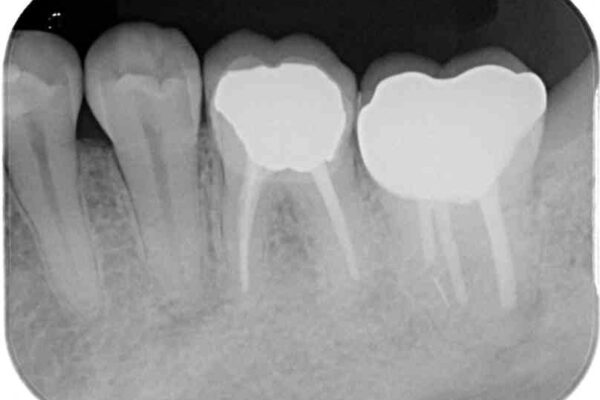

治療前

• 海外赴任前に治したい 割れてしまった奥歯のオールセラミッククラウン 治療前画像